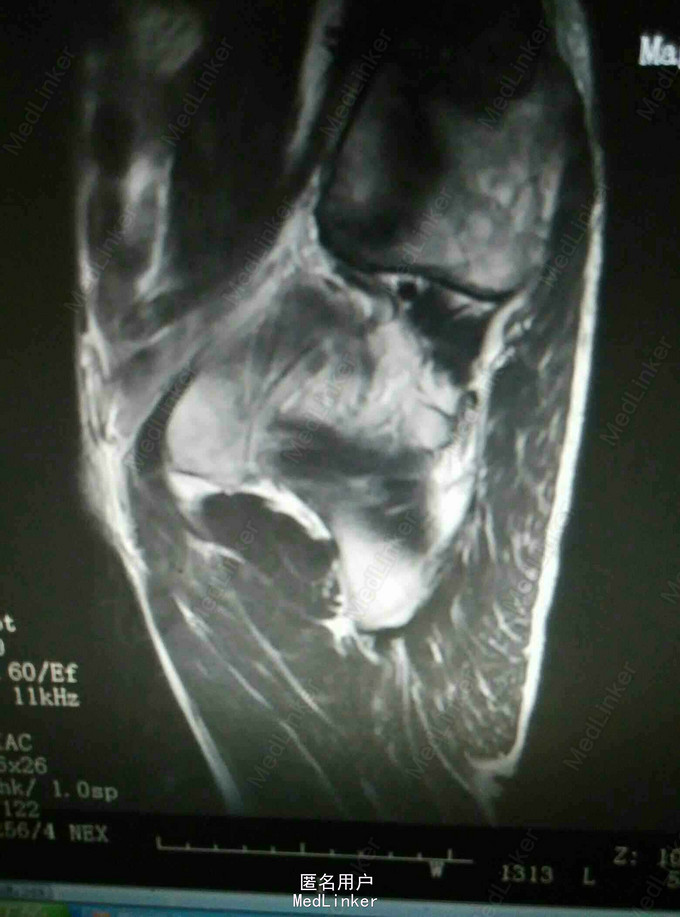

查体:腹部未及明显包块,四肢查体无异常,右臀部可及一5cm*3cm大小包块,质硬活动度差,边界不清。 复查:外院CT提示髂骨及骶骨翼骨质破坏,软组织肿块。 我院核磁提示髂骨骨质破坏软组织肿块,直肠距肛门1.5cm肠壁增厚肿块形成,考虑恶性肿瘤。 我院直肠镜检病理提示中分化腺癌

诊断:直肠癌 骨盆转移癌 治疗:建议我院肿瘤科专科治疗,患者拒绝,自动出院